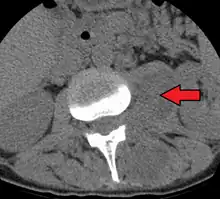

| Paraspinal abscess in the psoas muscle | |

Psoas abscess is a collection of pus in the iliopsoas muscle compartment.[1][2] It can be classified into primary psoas abscess (caused by hematogenous or lymphatic spread of a pathogen) and secondary psoas abscess (resulting from contiguous spread from an adjacent infectious focus).[2]